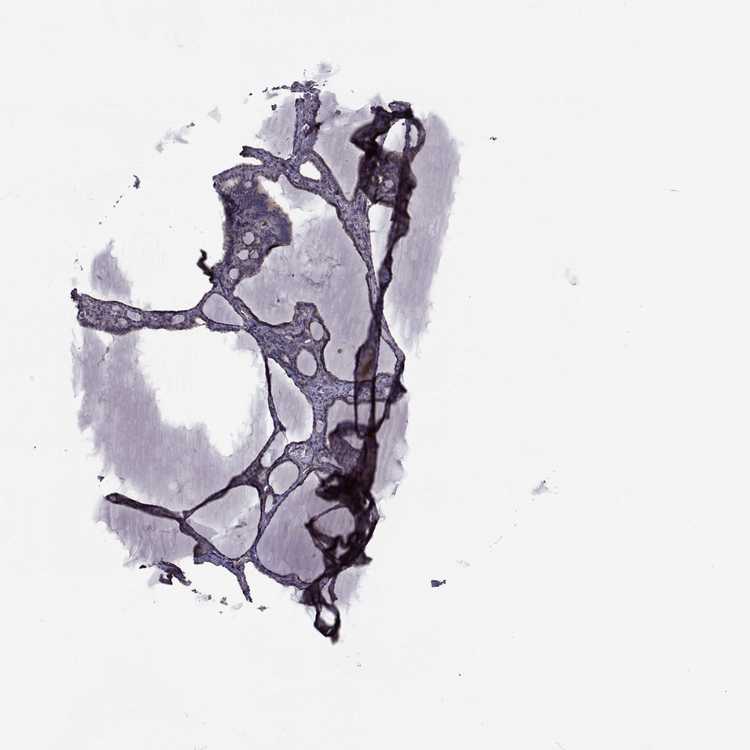

THYROID GLAND - Antibody stainingi

Antibody staining in the annotated cell types in the current human tissue is reported as not detected, low, medium, or high, based on conventional immunohistochemistry profiling in selected tissues. This score is based on the combination of the staining intensity and fraction of stained cells.

Each image is clickable and will lead to virtual microscopy that enables deeper exploration of all samples and also displays staining intensity scores, fraction scores and subcellular localization as well as patient and tissue information for each sample.

Antibody HPA072625Antibody HPA073886

Glandular cells LowNot detected